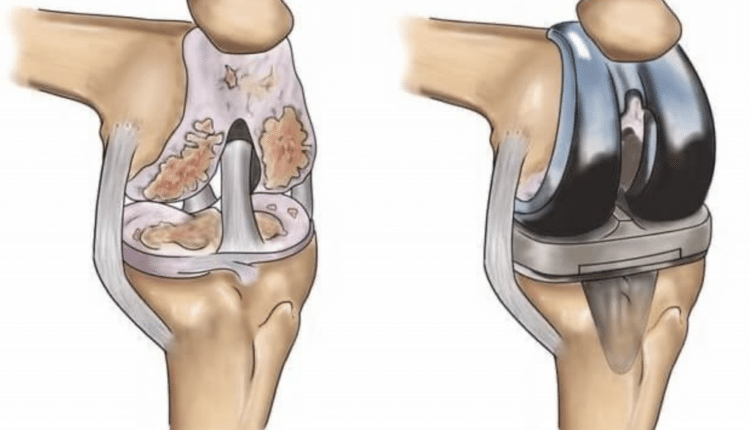

Ameliyat süreci, hastanın genel sağlık durumu ve diz ekleminin hasar derecesine bağlı olarak değişebilir. Diz protezi ameliyatı, diz ekleminin hasarlı kısımlarının çıkarılarak yerine metal ve plastik bileşenlerden oluşan yapay eklem parçalarının yerleştirilmesini içerir. Bu yapay eklemler, doğal eklemin fonksiyonlarını taklit eder ve hastanın hareket kabiliyetini büyük ölçüde geri kazandırır.